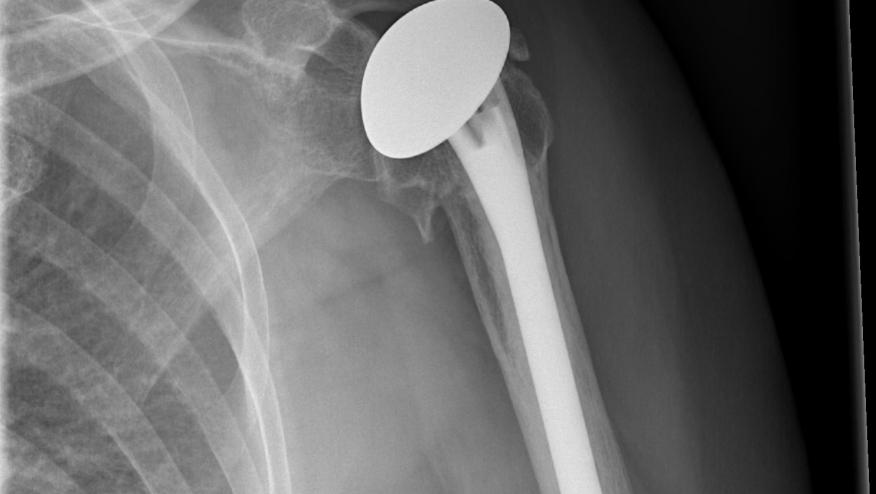

A systematic review of the outcomes of total shoulder replacements (TSR), humeral hemiarthroplasties, and reverse total shoulder replacements finds that approximately 90% of shoulder replacements last for longer than 10 years with good patient-reported outcomes.

This metanalysis included nine articles (ten series with 529 total shoulder replacements and 364 humeral hemiarthroplasties) analyxing survival and six articles assessing patient reported outcomes.

The estimated 10-year survival for total shoulder replacement was 94·6% (95% CI 93·6–97·6) and humeral hemiarthroplasties was 90·4% (87·0–94·0).

A single registry of 7651 total shoulder replacements, 1395 humeral hemiarthroplasties, and 7953 reverse total shoulder replacements was pooled. The pooled registry 10-year survival was 92·0% (95% CI 91·0–93·0) for total shoulder replacement, 85·5% (83·3–87·7) for humeral hemiarthroplasties, and 94·4% (93·4–95·7) for patients with osteoarthritis who had reverse total shoulder replacement and 93·6% (91·1–95·8) for patients with rotator cuff arthropathy who had reverse total shoulder replacement.